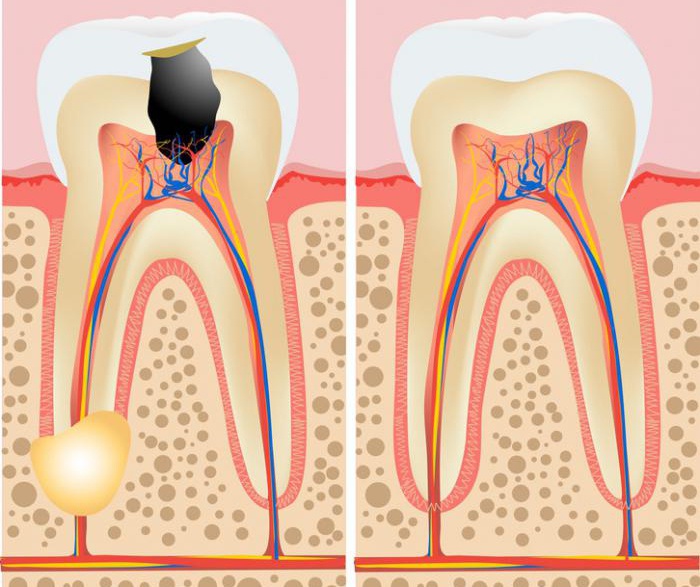

Cilj endodontskog tretmana je uklanjanje inficiranog ili oštećenog živca (pulpe), temeljno čišćenje i dezinfekcija kanala, te njihovo hermetičko zatvaranje kako bi se spriječila ponovna infekcija.

Pravovremenim tretmanom moguće je zaustaviti napredovanje bolesti i sačuvati prirodni zub, čime se izbjegavaju komplikacije i potreba za složenijim zahvatima.

Pravovremena terapija sprječava komplikacije i omogućava očuvanje prirodnih zuba bez potrebe za složenijim zahvatima.